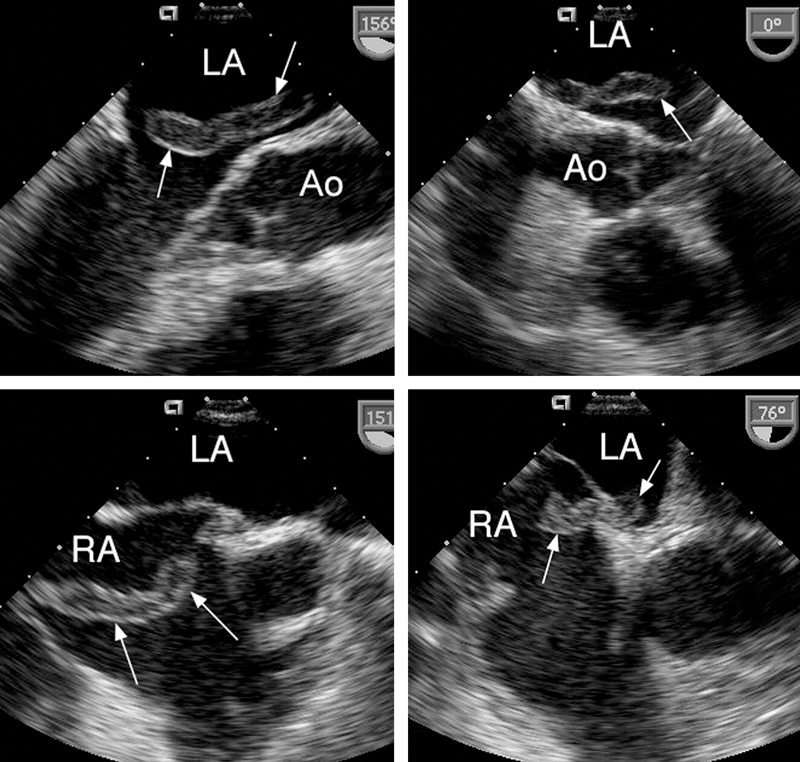

فحوصات تشخيصية لبعض امراض القلب والشرايين التاجية